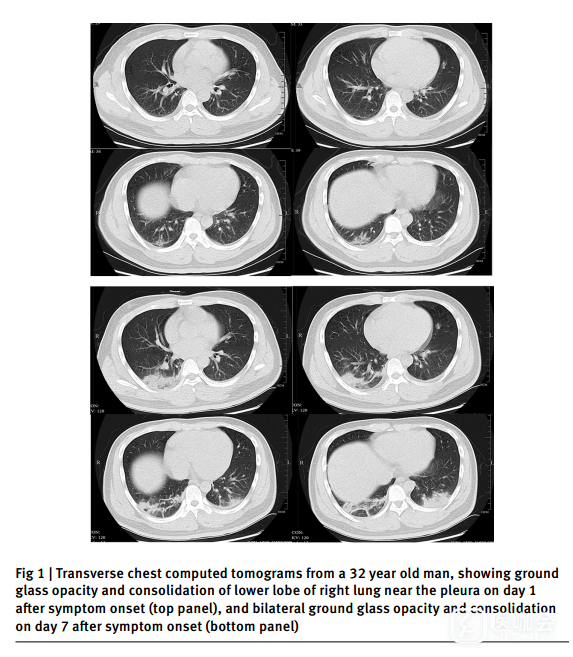

除1例患者外,其余患者的胸部CT或胸片均显示异常。52例(84%)患者的胸片显示肺部双侧受累(表2)。入院时感染患者的胸部CT典型表现为双侧多发小叶或亚节段实变或双侧磨玻璃影(图1)。只有一名患者没有出现肺炎相关症状。

图1. 一名32岁男性的胸部CT检查